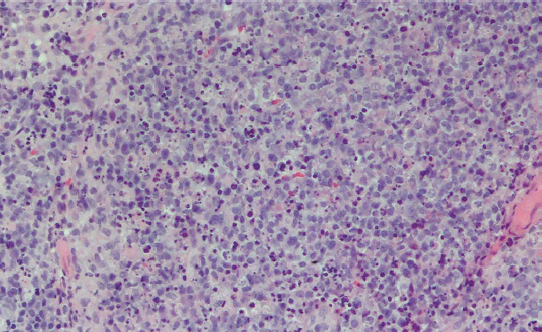

Keith E. Lewis, MD; Tracey Samko, MD; Erika Escobedo, MD; Daniel Im, MD; Jenny L. Wong, cPed, Cfts, CCWS, DMD, MD; Cynthia H. Ho, MD; Randall Y. Chan, MD

An 18-year-old boy presented with fever, weight loss, gingival enlargement, and pain for 2 weeks. On physical examination, he had generalized...